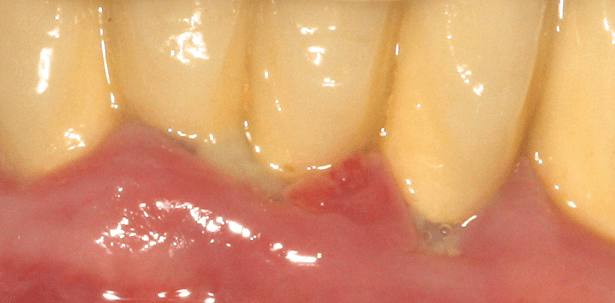

Bei der intraoralen Befunderhebung werden die Tonsillen, der Rachenring, die Schleimhäute des harten und weichen Gaumens, die Wangenschleimhäute, die Zunge, der Mundboden und das Vestibulum inspiziert. Diese Untersuchung ist auch wegen eines erforderlichen Krebs-Screenings und Identifizieren von Mundschleimhauterkrankungen von besonderer Bedeutung und sollte sorgfältig durchgeführt werden (Abb. 1 und 2). Weiterhin sollte ein kurzer funktioneller Befund erfasst werden. Dabei werden die Kaumuskulatur und das Kiefergelenk palpiert und die Zähne werden auf Schlifffacetten hin untersucht. Gegebenenfalls wird die statische und dynamische Okklusion überprüft. Die funktionelle Untersuchung ist von Bedeutung, da bekannt ist, dass Zähne mit okklusalen Diskrepanzen initial höhere Sondierungstiefen aufweisen5 und unbehandelt die Progression einer Parodontitis gefördert wird.6 Entgegen anderslautenden historischen Annahmen ist eine Malokklusion allein aber kein auslösender Faktor für parodontale Läsionen. Bei der Beurteilung der Zähne ist auf Stellungsanomalien zu achten. Eng stehende und stark verschachtelte Zähne können als Plaqueretentionsnischen wirken, zwischen breiten Approximalräumen kann es vermehrt zu Speiseimpaktionen kommen. Weiterhin müssen vorhandene Füllungs- und Kronenränder auf Suffizienz und Passung überprüft werden. Alle kariösen Läsionen müssen erfasst werden. Erosionen, keilförmige Defekte, Ablagerungen und extrinsische sowie intrinsische Verfärbungen sind zu dokumentieren. Weiterhin ist die Mobilität der Zähne zu testen. Die Zahnlockerung wird mithilfe von zwei Instrumentengriffen bestimmt und in drei Grade eingeteilt. Bei Grad I ist die Zahnkrone bis etwa 1 mm auslenkbar, bei Grad II ist die Krone mehr als 1 mm auslenkbar und bei Grad III ist der Zahn auf Lippen- und Zungendruck und/oder in axialer Richtung beweglich. Eine Zahnlockerung kann Ausdruck eines stark vorangeschrittenen Attachmentverlustes sein, aber auch durch funktionelle Überbelastung verursacht werden. Abschließend sollten noch die Perkussionsempfindlichkeiten der Zähne sowie Vitalitätsproben durchgeführt werden.